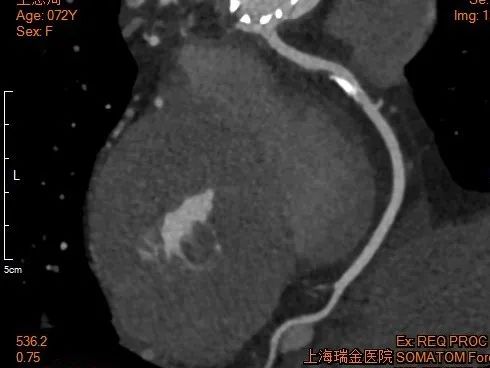

冠脉造影

RCA

下缘高度 10.2mm

上缘高度 11.9mm

瓣叶长度 12.7mm

LCA

下缘高度 7.1mm

瓣叶长度 11.8mm